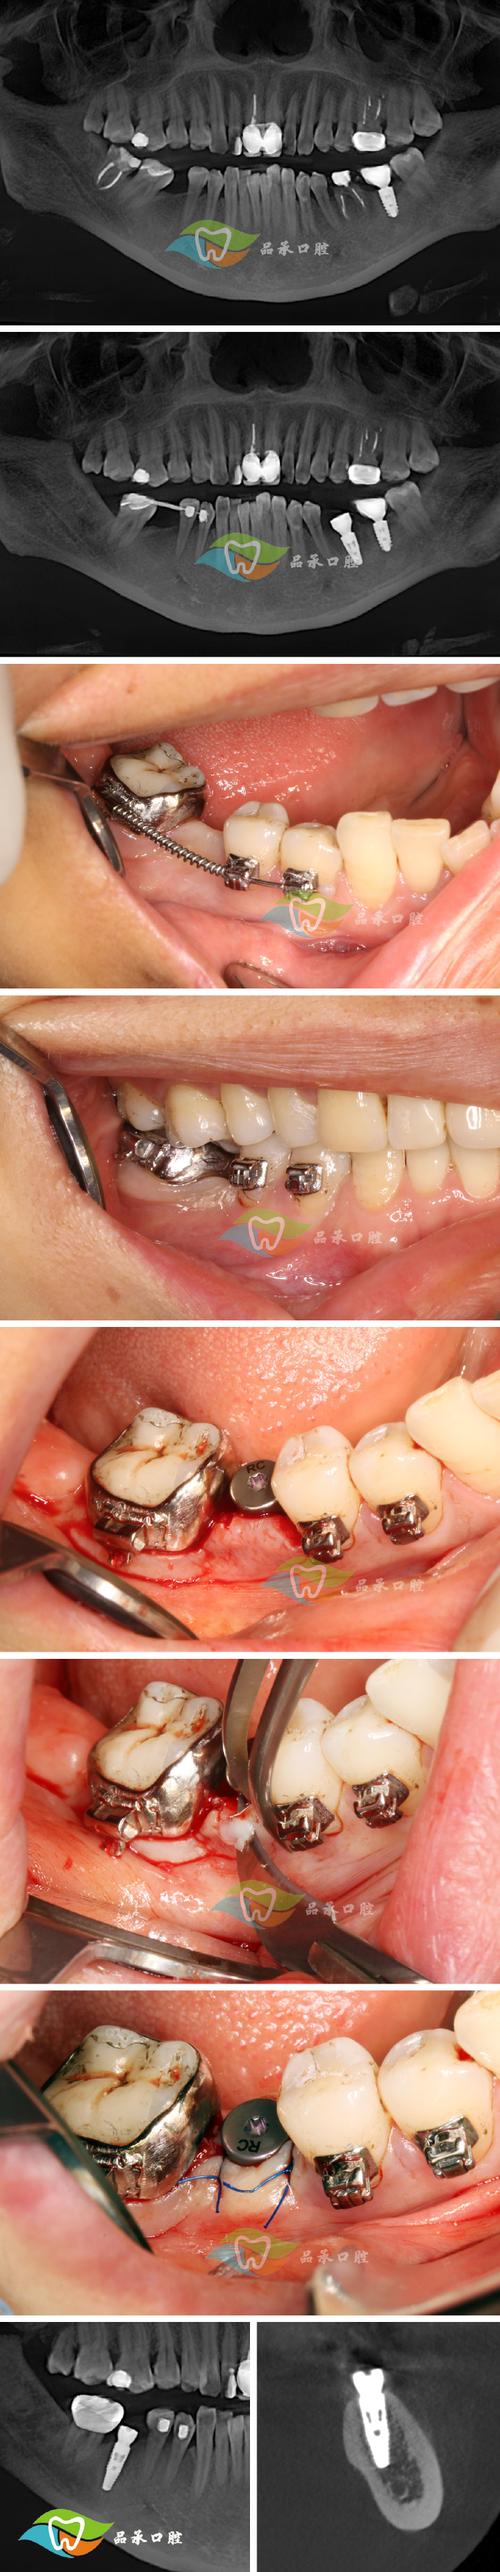

无论是阻生智齿、埋伏多生牙、牙周病松动牙,还是正畸需要拔除的前磨牙,超声刀都能轻松应对,尤其对于传统拔牙难度高的“水平阻生智齿”“埋伏齿”,超声刀能通过“分根切割”的方式,逐块取出,减少创伤。

拜博口腔引进德国超声骨刀系统(如Piezosystem 7000),配合3D-CBCT、数字化口扫等设备,能在术前清晰呈现牙齿位置、牙根形态、神经走向,制定“一人一策”的拔牙方案,对于阻生智齿,医生会通过CBCT测量牙齿倾斜角度、与邻牙距离,规划超声刀的切割路径,避免“盲目操作”。

拔牙效果的关键在医生,拜博口腔的拔牙医生均具备10年以上临床经验,尤其擅长复杂牙列拔除,他们不仅熟练掌握超声刀操作技巧,还能结合传统拔牙方法,应对各类突发情况,对于完全骨埋伏的阻生齿,医生会先用超声刀去除表面骨组织,再分根取出,避免大范围翻瓣,减少创伤。